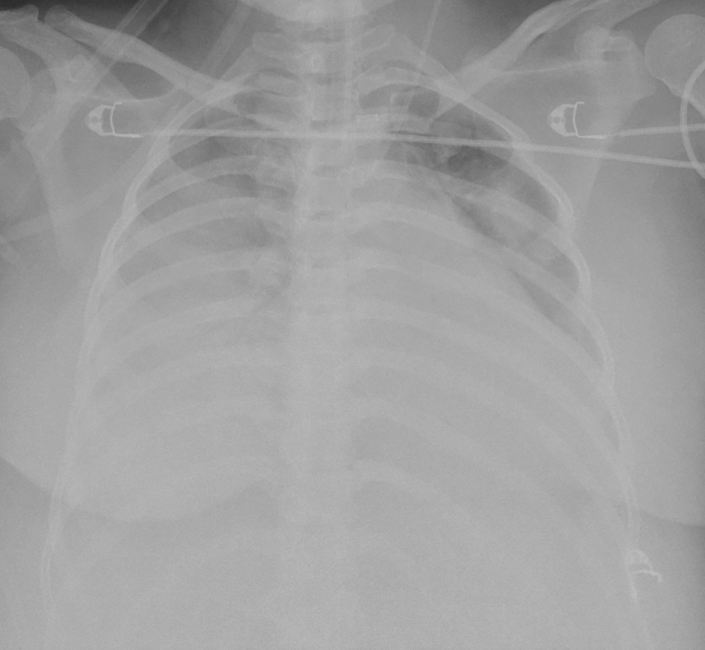

Nhận định về ca bệnh, ThS.BS Giang Minh Nhật – Trưởng đơn vị Hồi sức tích cực tim mạch – Bệnh viện Nhân dân Gia Định cho biết : “Khi được chuyển đến bệnh viện Nhân dân Gia Định, tình trạng suy hô hấp của bệnh nhân diễn tiến nguy hiểm đến tính mạng (hội chứng nguy kịch hô hấp cấp) không đáp ứng thở máy xâm lấn, tổn thương phổi trên Xquang ngực chiếm hơn 80% thể tích phổi. Sản phụ P. được can thiệp VV-ECMO (oxy hoá máu màng ngoài cơ thể) cấp cứu vì suy hô hấp giảm oxy máu kháng trị. Sau can thiệp VV-ECMO và lọc máu liên tục 14 ngày, tình trạng suy hô hấp và tổn thương thận cấp của sản phụ P. hồi phục ngoạn mục, tổn thương gan, giảm tiểu cầu và tán huyết đều ổn định. Hội chứng nguy kịch hô hấp cấp (ARDS) chiếm khoảng 8% bệnh nhân có hội chứng HELLP nặng, với nguy cơ tử vong xấp xỉ 50%. Can thiệp ECMO ở sản phụ có hội chứng HELLP thường có nguy cơ chảy máu trong quá trình thủ thuật và theo dõi rất cao do số lượng tiểu cầu trong máu giảm nặng, đòi hỏi cần có chiến lược điều trị kháng đông hợp lý.”